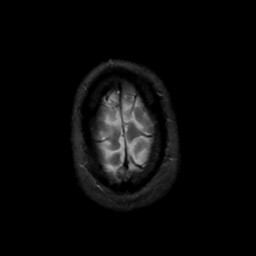

MR Study #15, June 9, 1991 -- Slice #46

[Home][Help][Clinical][Tour 1][Tour 2] Slice 46